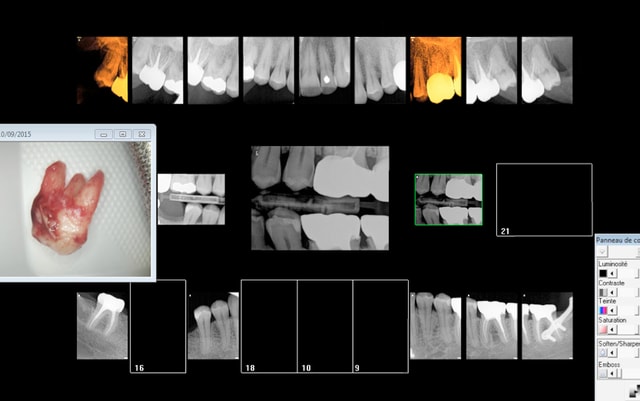

Signe d'appel : atcd de soins intensifs, douleur diffuse.

Amuses toi. Quoi coter "judicieusement" ? -)))))

Et pourquoi sauf 3 ième molaire pour les rétro alvéolaires ?